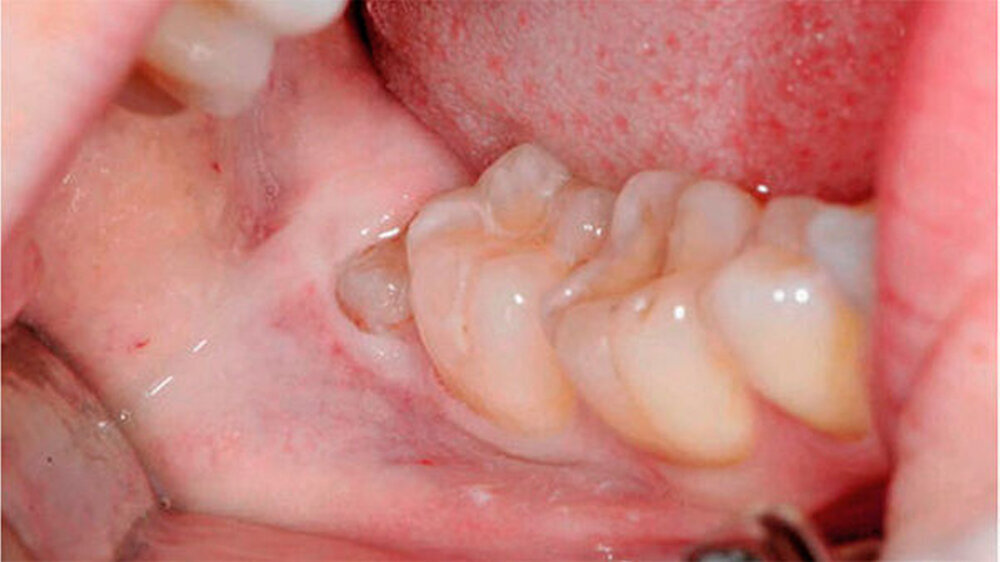

Bei der 27-jährigen, gesunden Patientin, kam es zu rezidivierender Perikoronitis des teilretinierten Zahns 48 (Abb. 1a). Primär wurde eine OPT-Aufnahme zur Operationsplanung erstellt (Abb. 1b). Dabei zeigte sich eine komplette Überlagerung der Zahnwurzel über den C. mandibulae. Zur weiteren Abklärung der Lagebeziehung wurde eine DVT-Aufnahme erstellt (Abb. 1c). Eine linguale Lage des C. mandibulae zur Zahnwurzel konnte festgestellt werden. Eine knöcherne Begrenzung des C. mandibulae zur Zahnwurzel fehlte.